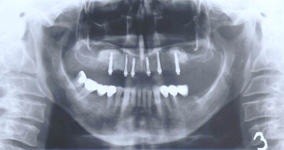

Při ztrátě molárů a premolárů v horní čelisti a jejich náhradě implantáty se často setkáváme s nedostatečnou vertikální nabídkou kosti pod čelistní dutinou, často doprovázenou i nedostatečnou horizontální nabídkou a sníženou kvalitou kosti

(v oblasti 2. premoláru v 50%, v oblasti moláru až v 80% případů nedostatečná kostní nabídka)

Od roku 1985 je tento problém řešen augmentační operací nazývanou sinus lift.

Jedná se o vyzvednutí membrány, která čelistní dutinu vystýlá, pod vyzvednutou membránou vznikne kapsa, kam se umístí augmentační materiál, do kterého se zavedou implantáty.

Vhojení implantátů se při této operaci prodlužuje na 6-12 měsíců.